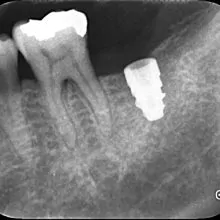

こちらが術後のレントゲンです。

シミュレーションとほとんど同じ位置に埋入できました🦷